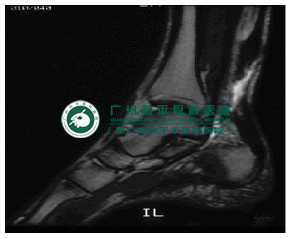

急性断裂通过仔细询问病史和物理检查很容易确诊。慢性跟腱断裂患者常常主诉持续疼痛和(或)无力。可能有一个急性损伤病史,之后症状开始出现。影像学上MRI可明确诊断。